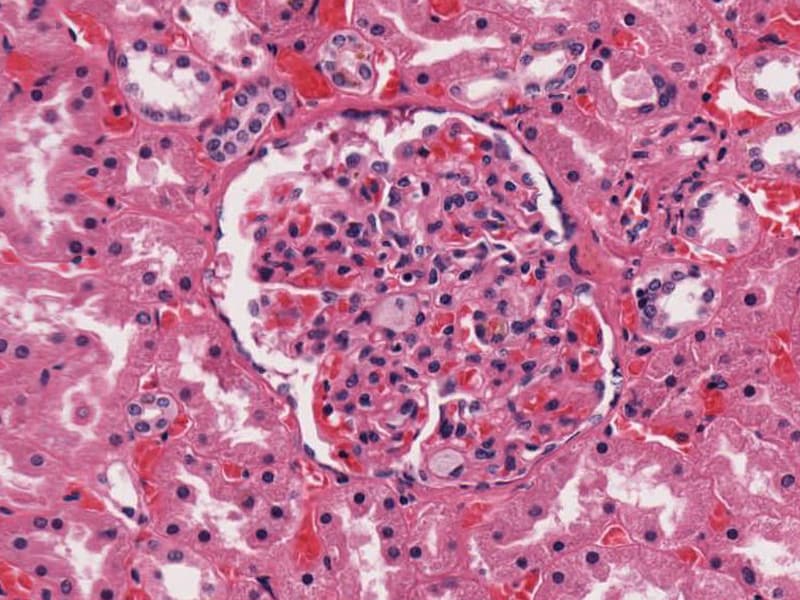

Болезнь Нимана-Пика Тип А: Симптомы и лечение

Раздел: Визуальный дайджест